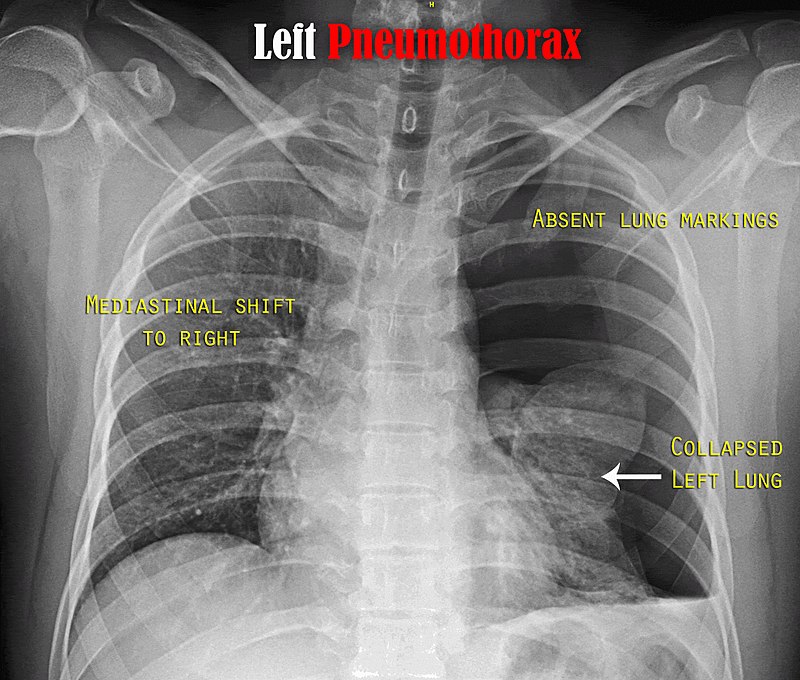

Pneumothorax

Pneumothorax is air buildup in the pleural space.

Pneumothorax leads to collapse of a portion of the lung.

The trachea shifts to the same side of the collapse.

The trachea is pulled in the opposite direction of the wound.